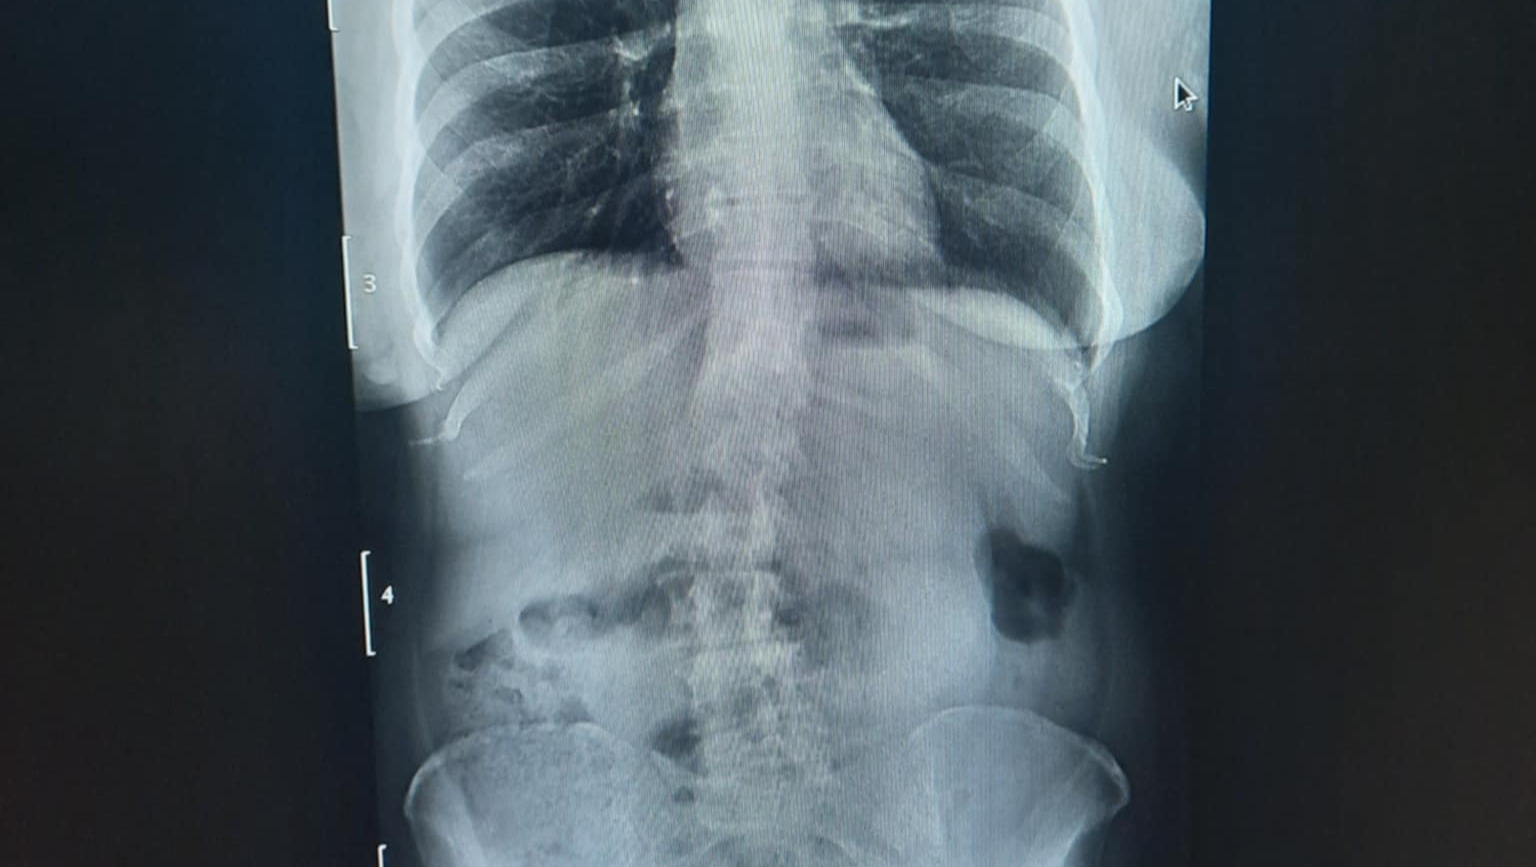

XRay indicates Double Curve (S-shaped) Scoliosis

Scoliosis Location: thoracic, and lumbar (dominant) regions.

9/9/2025-recomended for ALIF (anterior lumbar interbody fusion) Surgery for fusions of L2, L3, L4 & L5 with disc replacement between those (3 cages).

FINDINGS: Transitional anatomy of the lumbar spine is

suspected, but For the purposes of this exam, the final disc

bearing segment will be designated L5-S1. There is a broad

dextroconvexed curvature of the lumbar spine seen on the

scout exam with grade 1 anterolisthesis of L5 upon S1

measuring 6.4 mm. No other spondylolisthesis is evident.